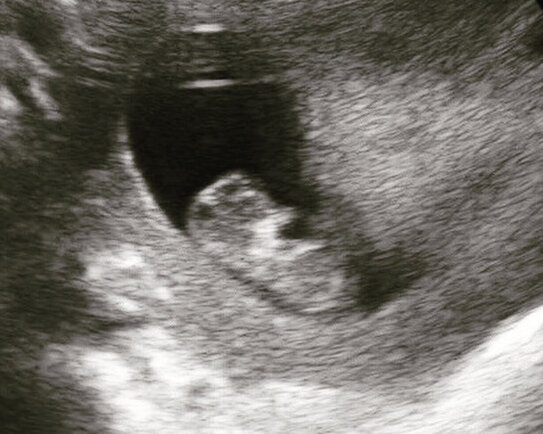

Фото автора | Мой первый триместр